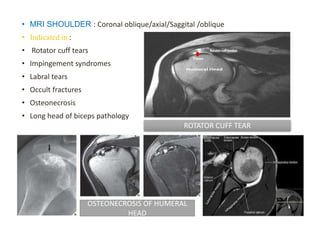

• MRI SHOULDER : Coronal oblique/axial/Saggital /oblique

• Indicated in :

• Rotator cuff tears

• Impingement syndromes

• Labral tears

• Occult fractures

• Osteonecrosis

• Long head of biceps pathology

ROTATOR CUFF TEAR

OSTEONECROSIS OF HUMERAL

HEAD